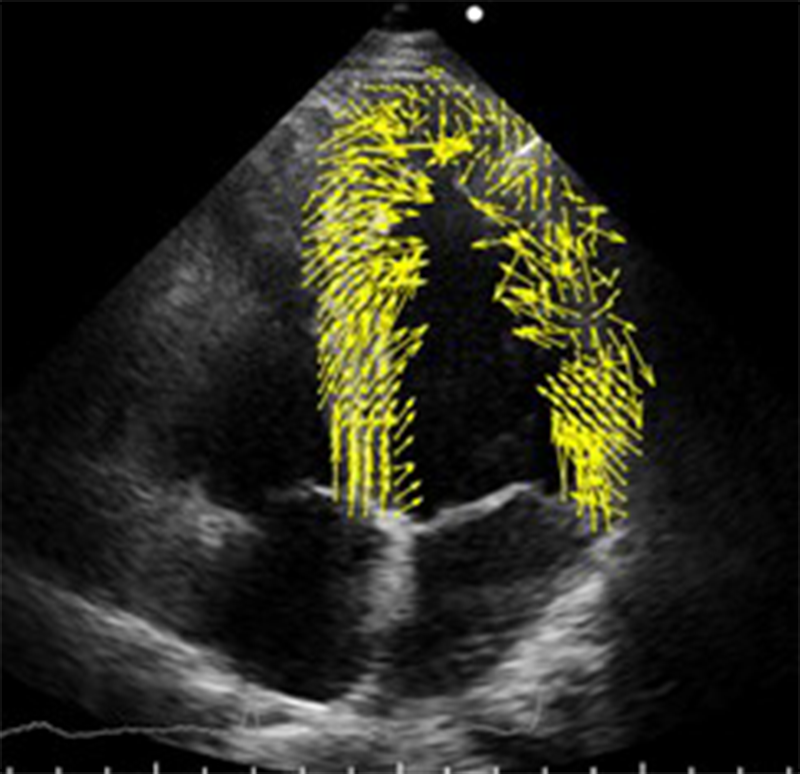

- 多数点のトラッキング:図1のように、心筋近傍の領域において多数のトラッキング点を設定してトラッキング処理し、それぞれの動きベクトル(黄矢印)を算出する。

図1 心筋近傍の多数の点をトラッキングして算出した動きベクトル

(収縮期、ベクトルの長さは実際の10倍で表示)